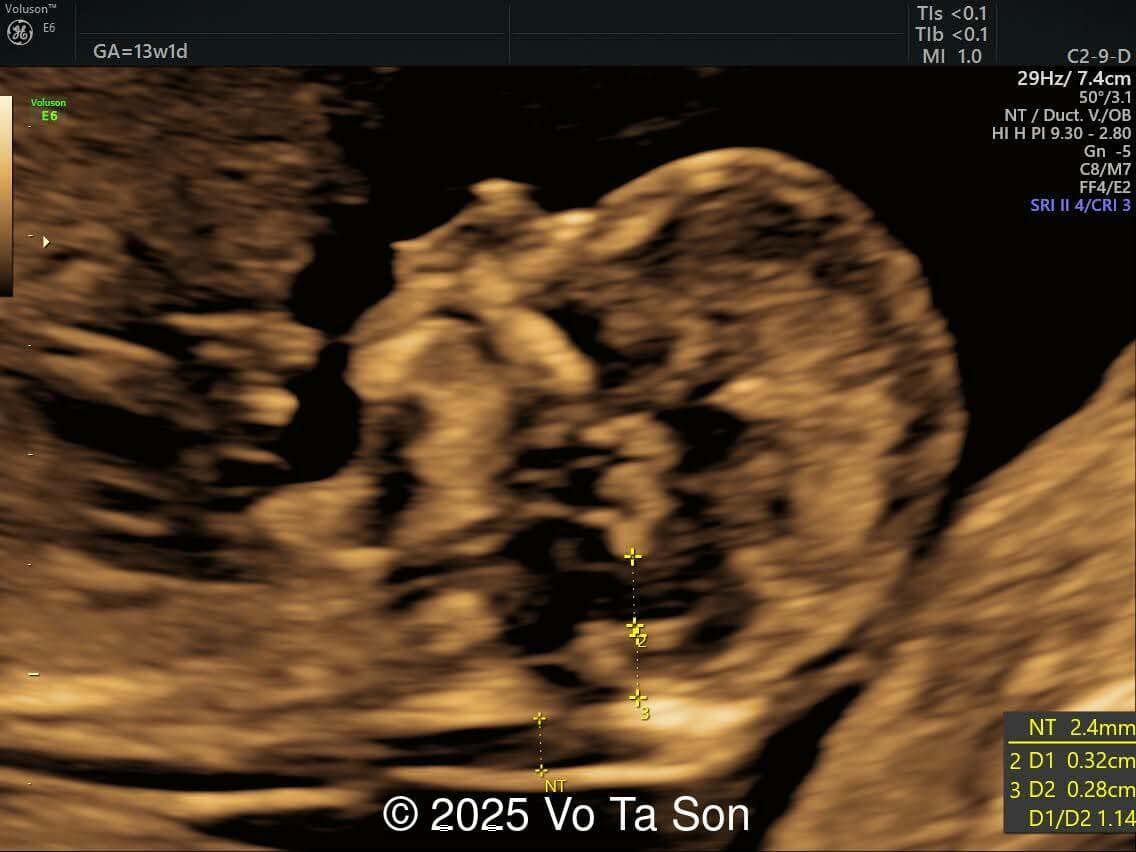

Mid-sagittal view of the brain

Image 3 Mid-sagittal view of the brain

• Open spina bifida in the sacral region with dry brain and crash sign, BS/BSOB >1, direct lesion at sacral coccygeal spine